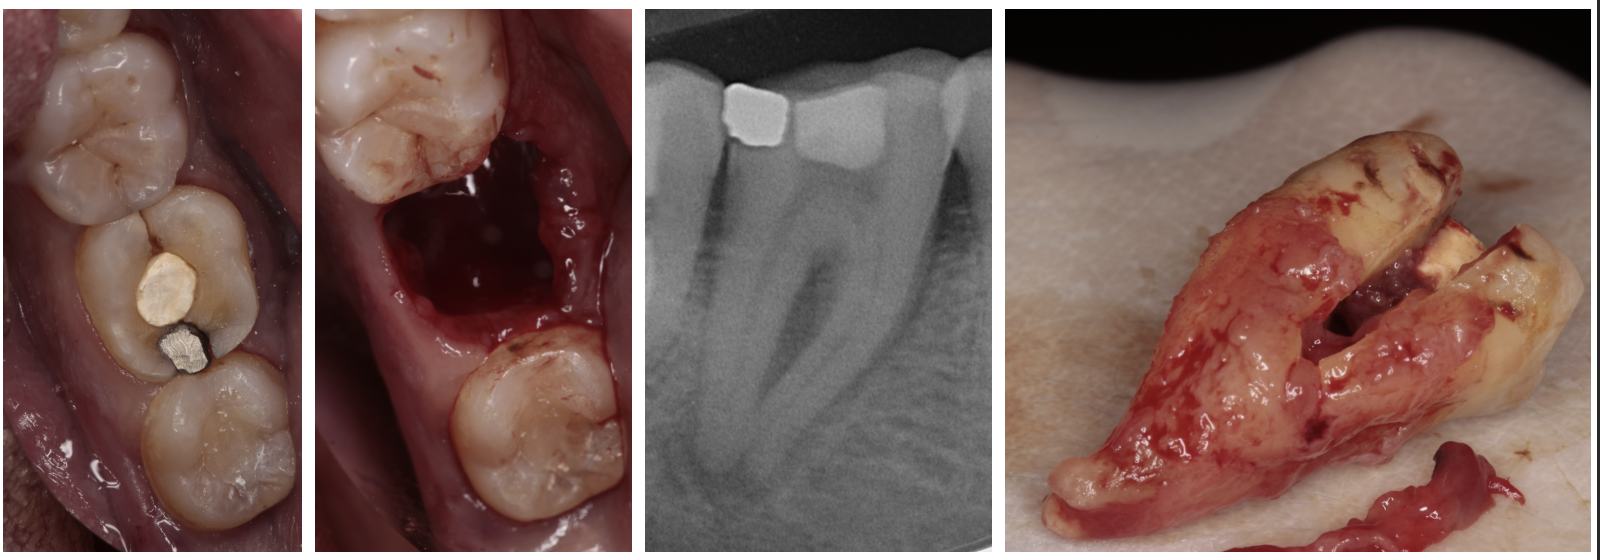

Autotrasplante

Consiste en la movilización de un diente al alvéolo de un diente que ha sido previamente extraído, estando indicado en pacientes en jóvenes y en crecimiento.